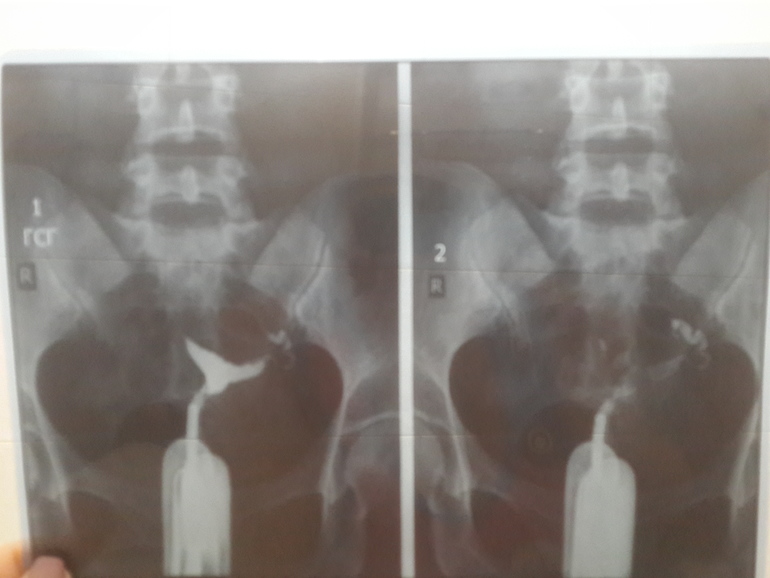

Гляньте снимок действительно проходимы???

Образ жизни до, во время и после ЭКОЗабрала снимок, сказали трубы проходимы, вообще не понимаю где трубы , тоненькие что ли, к врачу попаду через неделю, расшифруйте кто понимает???

Мне видится 1 проходимая, там контраст вышел в брюшную полость, а вторая нет. По этим снимкам. Может другие есть?

Как минимум одна ( левая ) не проходима. Я если честно думала что такую процедуру уже не делают. Она сильно облучает яйцеклетки. После неё несколько месяцев нельзя планировать. Сейчас как правило УЗИ с контрастной жидкостью делают.

Я имею ввиду левая - где сердце, на снимке она справа. У меня по ГСГ была ложная непроходимость, на лапаре все идеально проходимо. Там же и воздух, и спазм может быть.